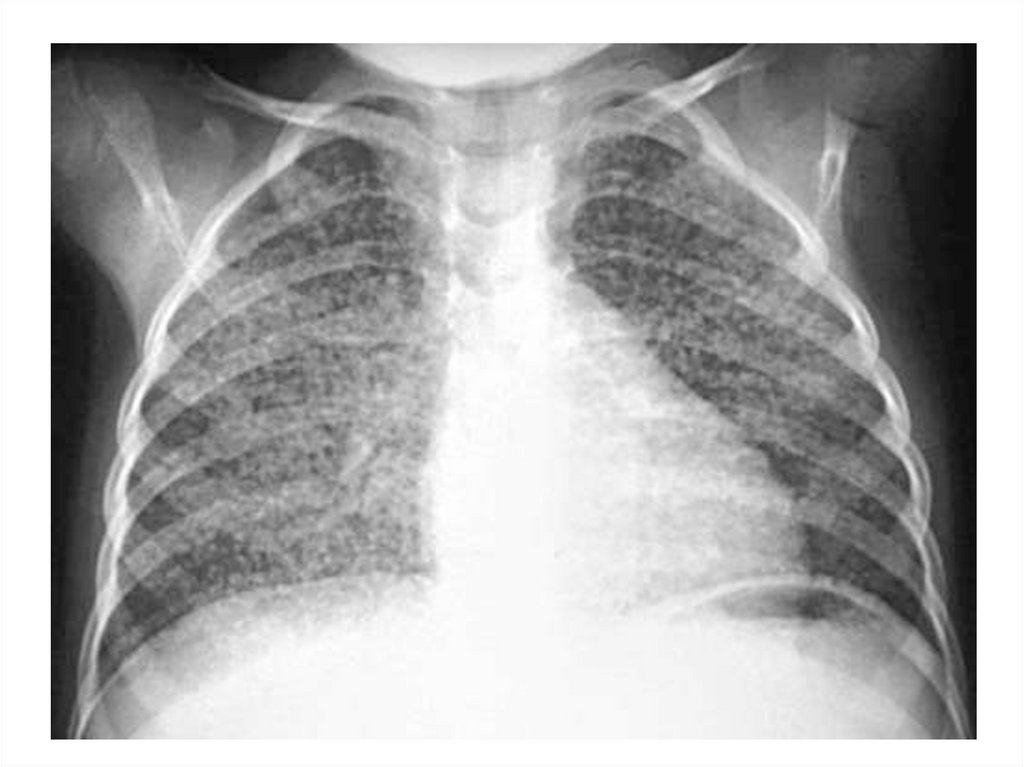

Пневмония

20.

21.